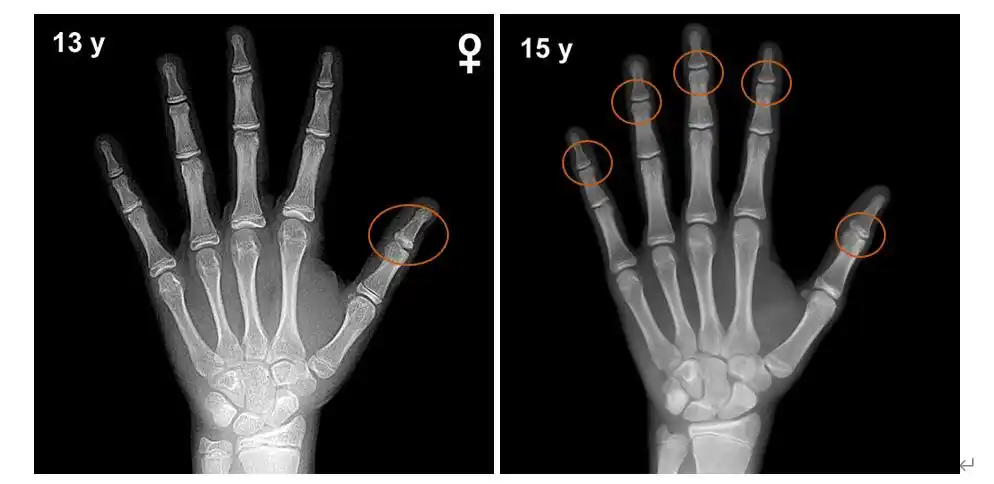

经过反复探索以及实验验证,科学界一致将手腕骨作为评价骨龄的最佳

收藏必备丨骨龄图谱

骨龄发现的象牙98骨骺-手腕关节x线 食指94骨骺出现 象牙状高密度